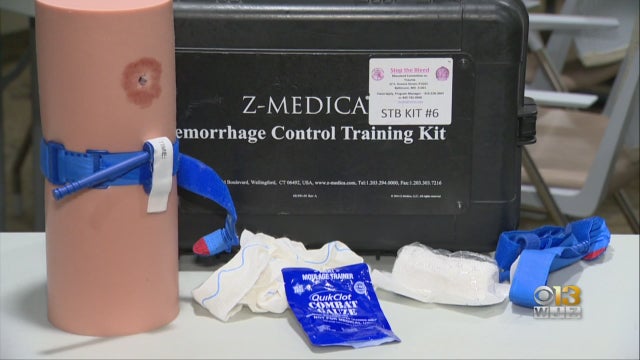

After two Baltimore area police officers were shot in the line of duty while serving a warrant earlier this month, the urgency of trauma response training in moments of chaos and danger took center stage.

In an emergency, seconds can be the difference between life and death.